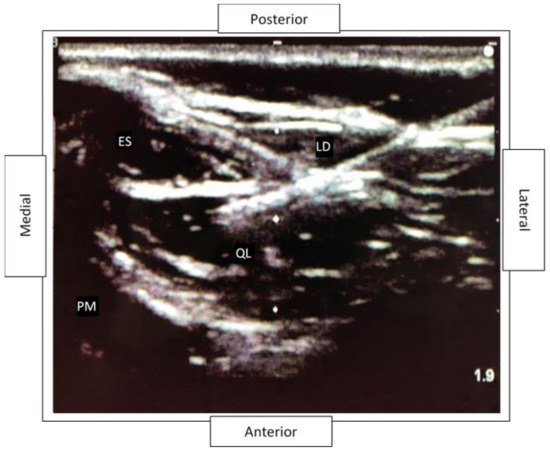

2.2. Quadratus Lumborum Block Details